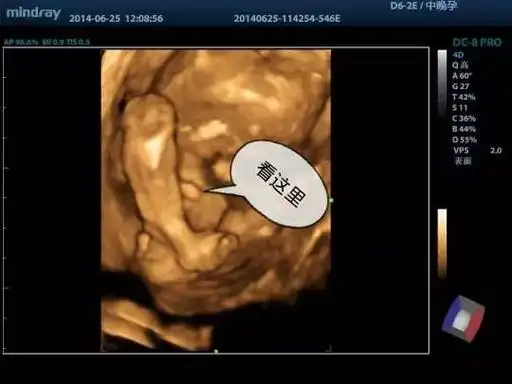

翻看昨天录的四维视频,被我看到了小鸡鸡

怀孕5个月四维彩超检查, 宝宝完全不配合, 医生直言: 这娃要不得_胎儿